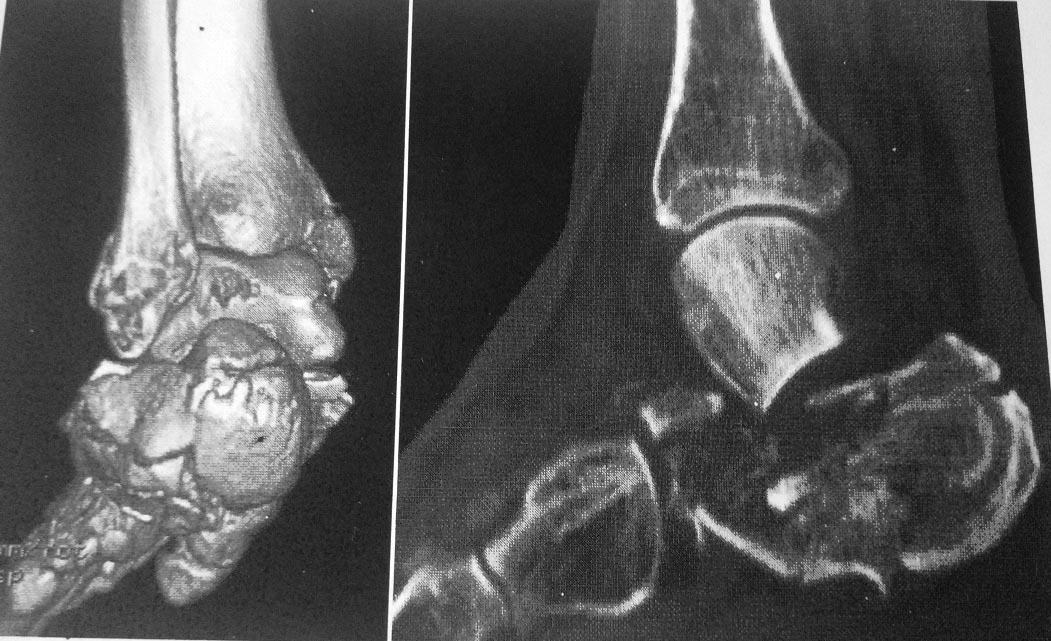

Дополнительно дооперационная СКт